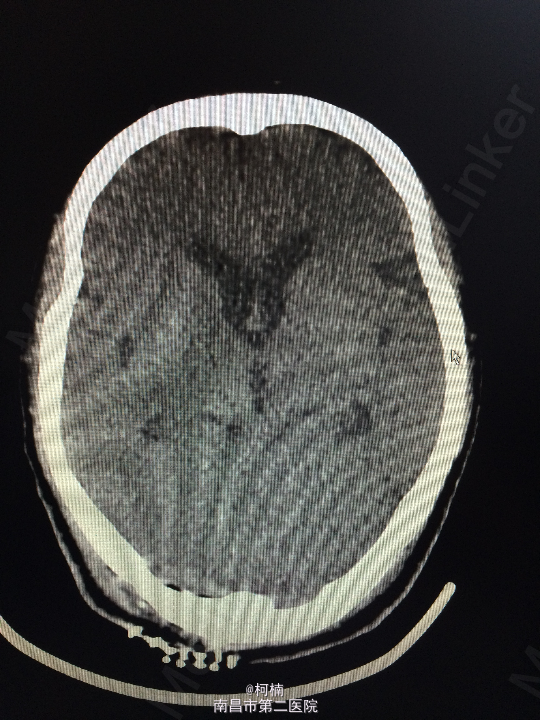

查体:神经系统体查未见明显异常 辅助检查:头颅MR提示右侧桥小脑区占位性病变,考虑脑膜瘤。四脑室狭窄,变形,幕上脑室积水,小脑扁桃体疝